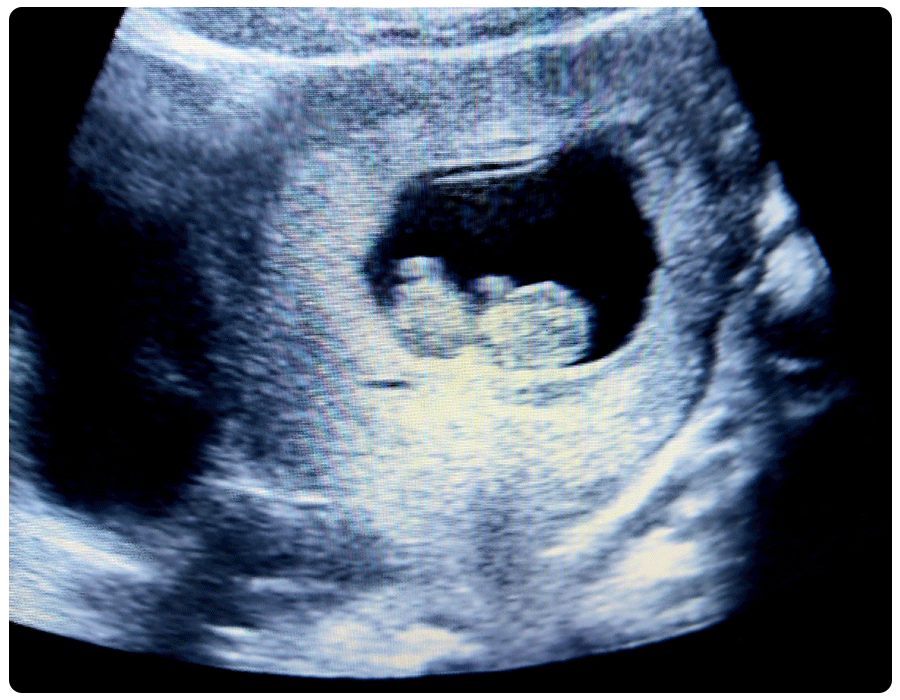

10 week ultrasound

Ten weeks is an important time if you’ve decided to have some first trimester genetic testing. Genetic testing is optional; which ones you choose to get—or not get—is up to you, but a genetic counselor can help you decide based on your family history and risk factors.

Most experts recommend a cell-free fetal DNA test, also known as a non-invasive prenatal test (NIPT). This is a blood test drawn at week 10 or later. It screens mom’s blood for signs of risk for Down syndrome, Edward Syndrome, Patau Syndrome and other chromosomal abnormalities.

In addition to the NIPT, your provider may also recommend or offer the nuchal translucency screening (aka NT Scan), which offers complementary, but slightly different information than the NIPT on the fetus’ risk of Down syndrome and other chromosomal abnormalities. The NT scan typically happens between weeks 10 and 14. For it, you’ll have a painless ultrasound, and baby’s nuchal fold (back of the neck) will be measured for signs of abnormality. The NTS is may be done as part of a “First Trimester Screen” where your blood is tested and your risk is assessed based on the results of both the ultrasound and the blood test. (Note: The First Trimester Screen blood test is different from the NIPT blood test. Whether or not you need to do a secondary blood test with the NT will vary based on your provider.)

Everyone waits for that first telltale flutter from baby, so you might be wondering if you can feel baby at 10 weeks? Even though baby is getting those practice kicks in, you’re unlikely to feel a fetus move before the second trimester, because those kicks and movements are just too small to sense at this early stage. Even if you don’t feel it quite yet, you can enjoy watching baby kick during your ultrasound!